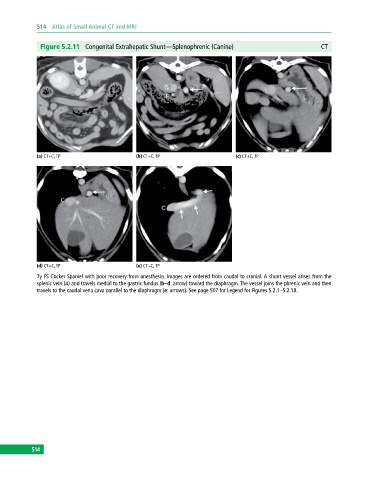

Figure 5.2.11 Congenital Extrahepatic Shunt—Splenophrenic (Canine) CT

(a) CT+C, TP (b) CT+C, TP (c) CT+C, TP

(d) CT+C, TP (e) CT+C, TP

7y FS Cocker Spaniel with poor recovery from anesthesia. Images are ordered from caudal to cranial. A shunt vessel arises from the

splenic vein (a) and travels medial to the gastric fundus (b–d: arrow) toward the diaphragm. The vessel joins the phrenic vein and then

travels to the caudal vena cava parallel to the diaphragm (e: arrows). See page 507 for Legend for Figures 5.2.1–5.2.18.